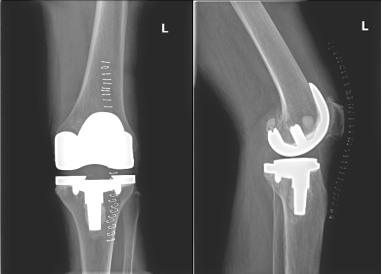

此病情困扰邱阿婆多年,严重影响日常生活,在我院住院期间,严格评估手术风险,精心准备手术,行左膝人工关节置换术,术后中西医结合诊治以及科学功能锻炼,术后1周可自行下地活动,术后2周可自行上下楼梯,术后1月可自行去市场买菜,日常生活基本可以自理。

术后X片: